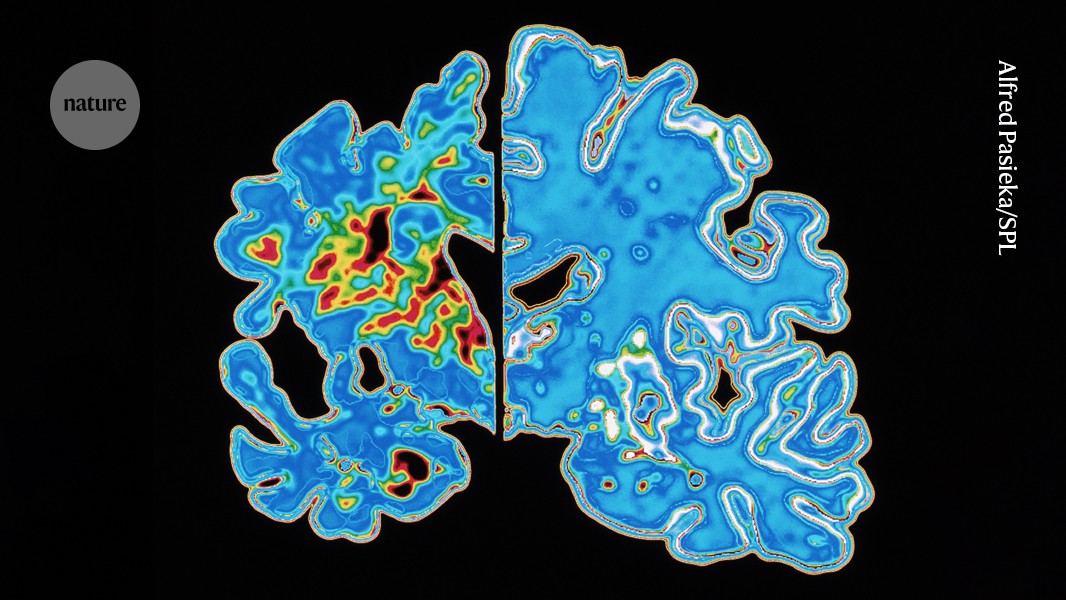

An abnormal form of the protein tau circulates in the blood and begins accumulating in the brain well before Alzheimer's symptoms such as memory loss appear. A blood test that measures this tau shows potential to act as a molecular clock to predict both whether and when Alzheimer's symptoms will develop. Early prediction could enable intervention at stages when treatment is more likely to be effective and provide a measurable biomarker to simplify and reduce the cost of clinical trials. Brain imaging can detect tau tangles but is cumbersome and expensive. In-home blood tests for this tau exist, but testing cognitively unimpaired individuals is not recommended until further validation.